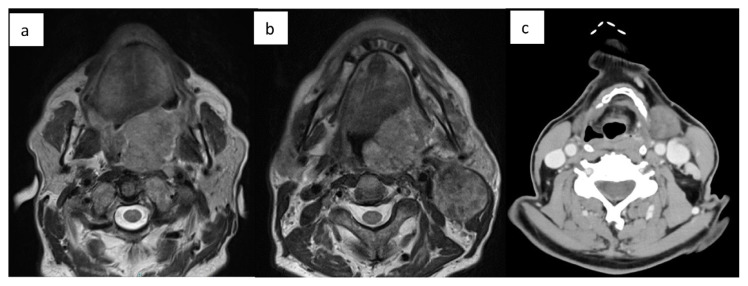

Abstract Image